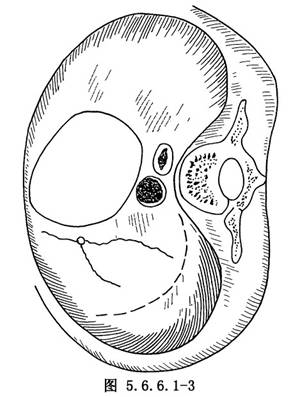

(2)切开膈肌:以左侧膈神经在膈肌上的附着点为中心,由外侧5~6cm处切开膈肌,弧形向两端扩大(图5.6.6.1-3)。出血点用缝扎法处理。在距食管裂孔2~3cm处的膈肌腹面有膈下血管横行越过,将其结扎后切断。用手指由食管裂孔穿过,将未切断的膈肌角用钳夹住切断,缝扎处理。